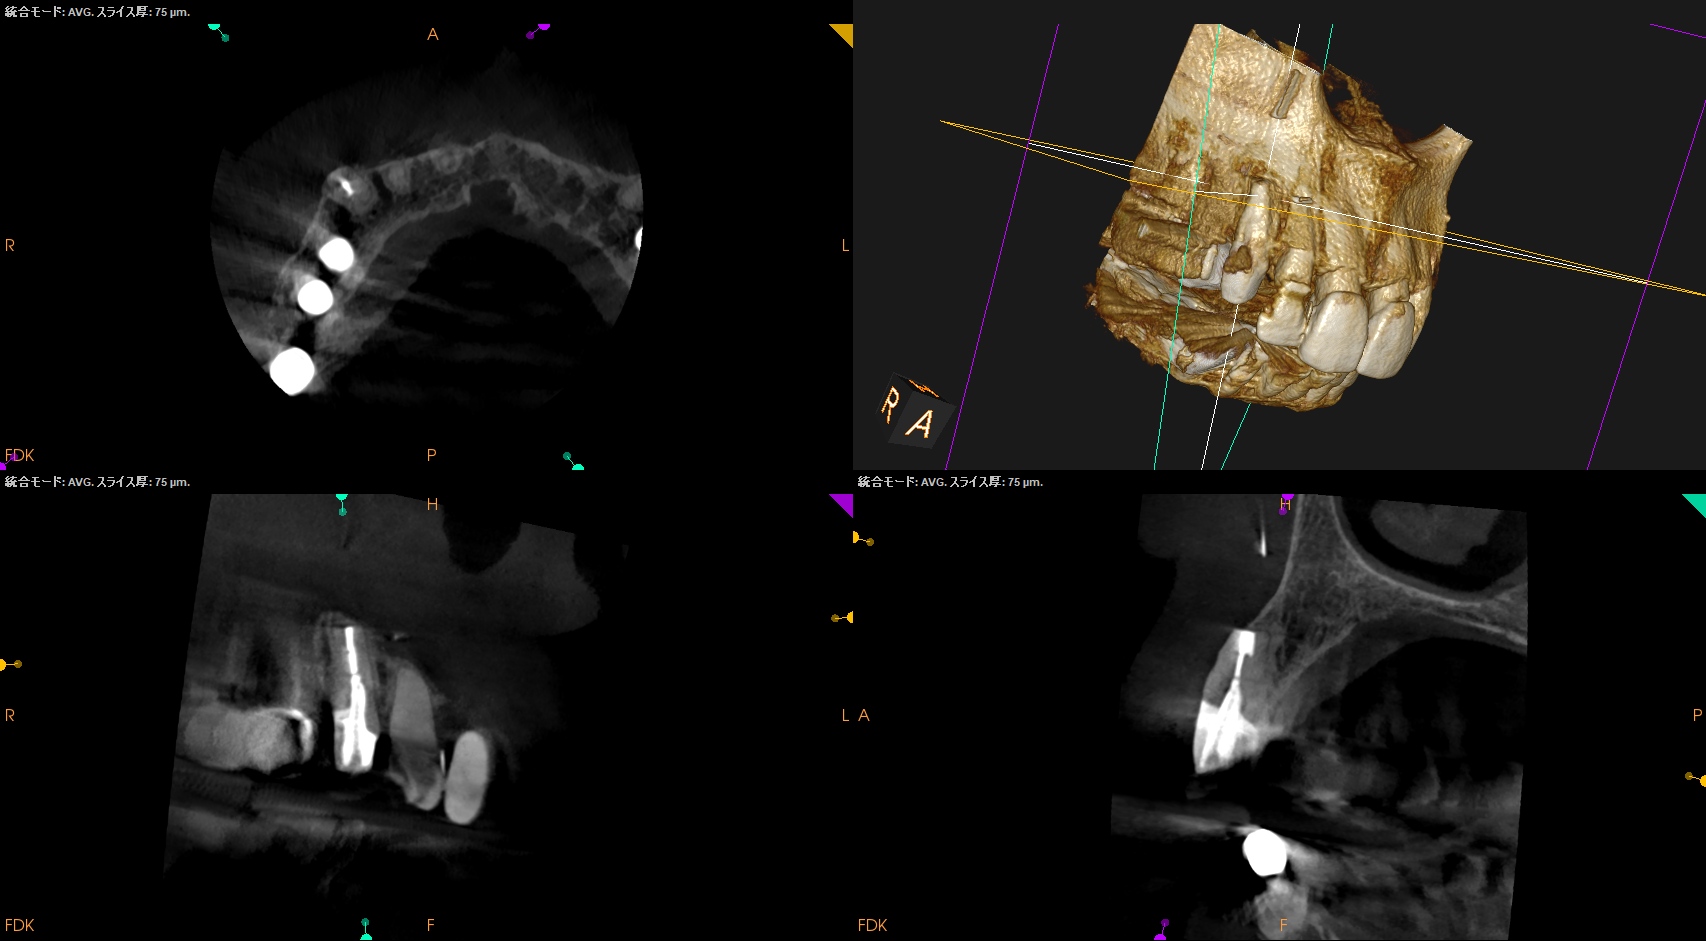

#6 Apicoectomy 10M recall(2025.9.3)

術直後と比較した。

90%がた治癒していると言えるだろう。

Gutta Percha Pointは除去できていないまま、なのにだ。

だからなんだろうか?

学術的にはマクロファージに貪食されるのでは?という意見があるが、真実はわからない。